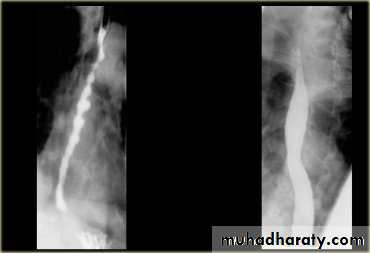

Narrowing :

1-the narrowing is Constant Short length (confined to cardia).

2-Regular and smooth.

3- No shouldering sign.

4-Tapering (Tip of pencil , cigar shape) Under left dome of diaphragm.

Achalasia continue

5. DILATATION (Sac like in proximal part )6-Undulating or spiky out line due to sluggish peristalsis.